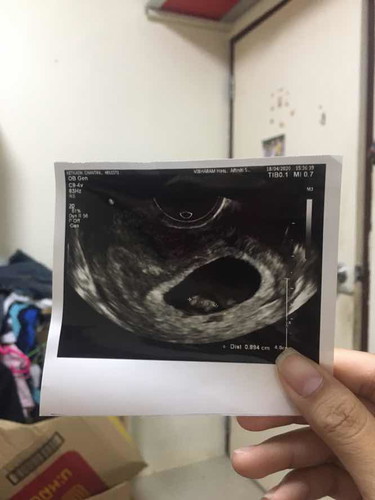

ท้องลูกแฝด คนแรกแท้งไปคนสองยังอยู่ ดูแลดีมาก บำรุงทุกอย่าง แต่สุดท้ายลูกก็ได้จากไป เสียใจมาก ทำใจไม่ได้เลย น้องอายุได้2เดือน